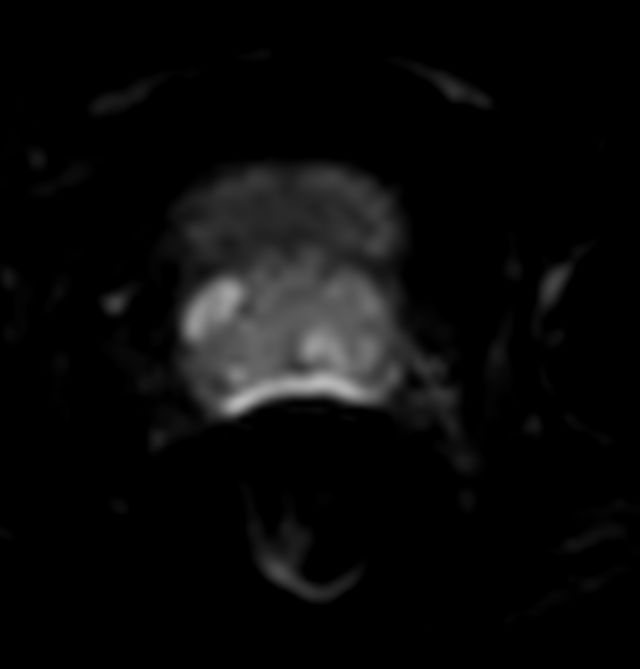

Diffusion - b800

Diffusion - b2000